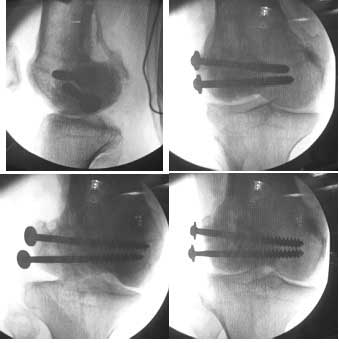

This 20 year old patient sustained a fracture in the lower end of the femur, one and a half years ago, with a compound wound over the fracture area. Notes at that time mention a compound fracture dislocation, with a loss of part of the lateral condyle. This was treated by debridement, and external fixation. After two weeks, the lateral condyle (coronal fracture) was fixed by a screw and k wire in an AP direction.

I opened it up from the lateral aspect.

Freed up the non-union site with minimal disturbance to the posterior and lateral soft tissue attachments on the lateral condyle fragment.

Applied a distractor between femoral shaft and tibia, to create a space on the lateral aspect.

This brought the lateral condylar fragment into a position that seemed to be reasonably well aligned, but showed up a bone gap.

This was fixed temporarily, bone grafted with tricortical struts, and fixed by two cancellous screws. The fragment was not large enough to afford any fixation to a plate or such implant, and the screws held it compressed well to the rest of the distal femur.

Post-op - limb is well aligned, rom 0-30, but I am not pushing that right now, for the next two or three weeks.

Pictures attached.

A good job, though personally I would have preferred the screws a bit longer.